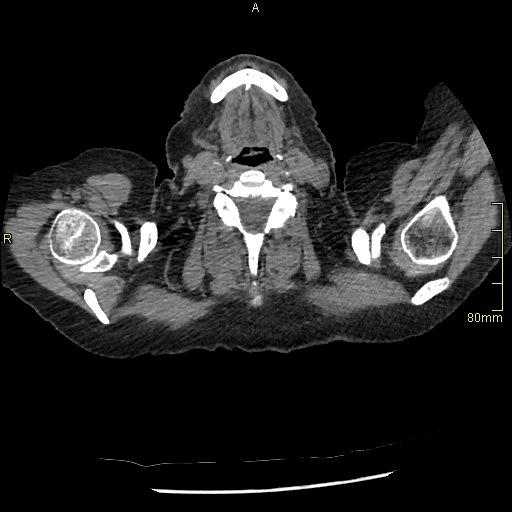

HRCT - Axial Supine Inspiration (Soft Tissue Window)